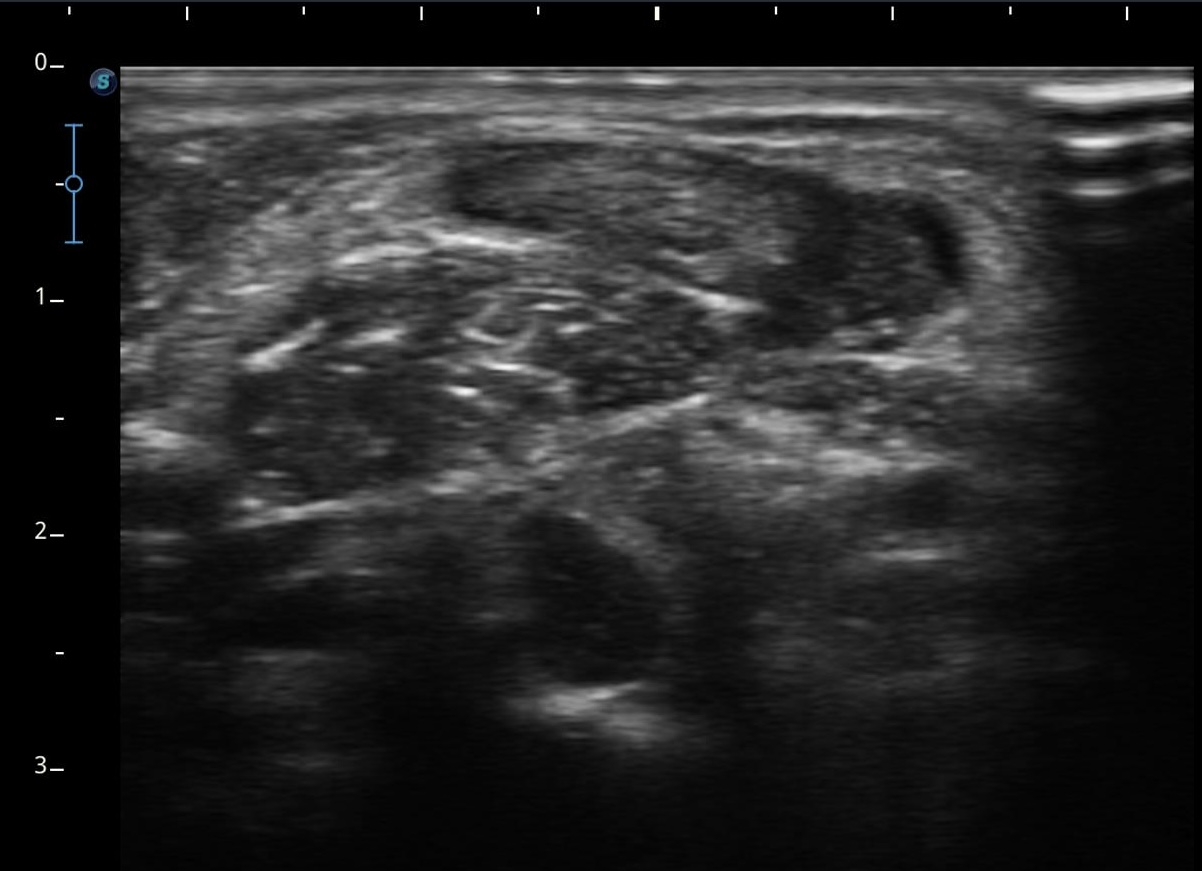

Se realiza ecografía clínica objetivándose ausencia de flujo en el interior de la luz, con imagen ecogénica en el interior compatible con trombo, no colapsándose a la presión con el transductor.

Sospechamos de trombosis venosa yugular externa (VYE). Se deriva a servicio de Urgencias para completar estudio.

Se realiza analítica de sangre (Dímero D 2029 ng/ml) y radiografía de tórax anodina. Se realiza eco-doppler cervical observándose trombosis de vena yugular externa izquierda al menos hasta su confluencia yugulosubclavia. Vena yugular izquierda no visualizada. Venas subclavia, axilar y braquiales izquierdas permeables sin datos de trombosis.

Se confirma nuestra sospecha diagnóstica: obstrucción total venosa central (OTVC) trombótica de la vena yugular externa.